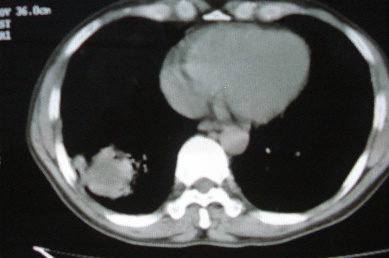

ct10716,男,59岁。发热咳嗽一天,咯血一次入院。

病灶中心有低密度,气体,病灶周围炎性浸润可能为肺脓肿,量体温、查个痰就是了,但肺脓肿一般都多少会有点兄水的。左肺下局部密度减低,小叶中心肺气肿。

病灶边缘较模糊,中心见低密度影及少量气影,宽基与胸膜相连,周围见炎性浸润,考虑右下肺脓肿。

病灶边缘较模糊,中心见低密度影及少量气影,宽基与胸膜相连,周围见炎性浸润,考虑右下肺脓肿。建议治疗后复查。

右下肺病灶,边缘模糊,中心见低密度坏死区及气体影,结合病史较短,以发热为主,考虑右下肺脓肿,建议抗炎治疗后复查。